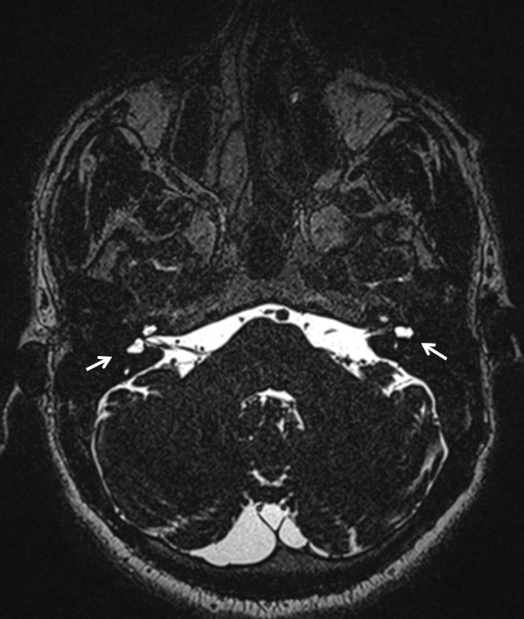

A 38-year-old man was admitted to our department due to recurrent sensations of imbalance and vertigo for two years. Moderate bilateral sensorineural hearing loss was detected. Magnetic resonance imaging demonstrated bilateral isolated aplasia of the lateral semicircular canals (Figure 1). Bilateral superior and posterior semicircular canals were normal. No cochlear malformation and no pathological contrast enhancement were detected. The internal auditory canal and the cerebellopontine angle were normal.

Figure 1: Axial CISS image shows bilateral isolated aplasia of the lateral semicircular canals (white arrows).